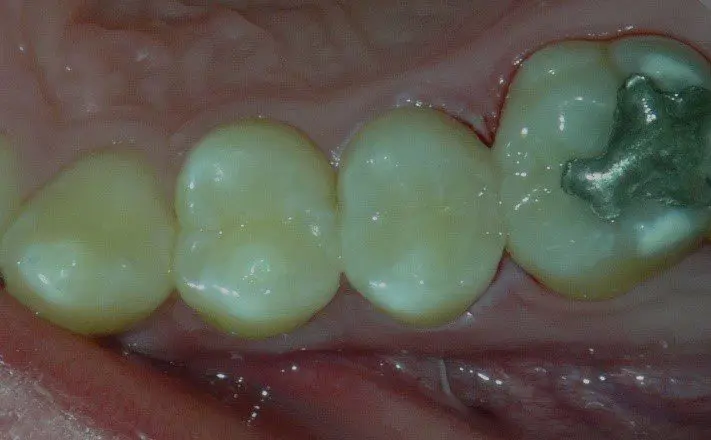

Figure 1: Shows rampant caries

Naomi was 10-years-old and suffered from acute dental phobia and rampant caries (Figure 1). She was so difficult to manage that she had not been able to receive treatment elsewhere. She was referred to me, which was not particularly convenient for her mother, who had to make the 40-mile drive to my office in Miami.